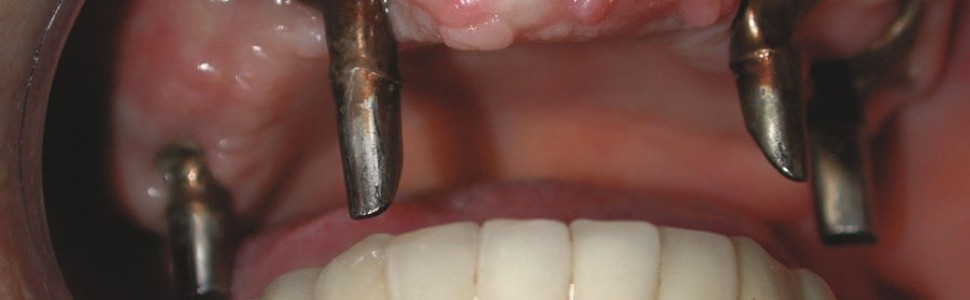

Pacjentka wyraża zgodę na zabieg chirurgiczny, polegający na wprowadzeniu wszczepów podokostnowych, zdając sobie sprawę, że jest to ostatnia deska ratunku, umożliwiająca stabilne zakotwiczenie protezy wspartej na wszczepach. Po zabiegu implantacji dwie oddzielne siatki podokostnowe (ryc. 3) zostaną ze sobą połączone (ryc. 4). Podniesiony płat śluzówkowo okostnowy (ryc. 5) ukazuje zgodność anatomii tkanki kostnej z modelem stereolitograficznym. Pozabiegowe zdjęcie pantomograficzne (ryc. 6) obrazuje idealne połączenie między dwiema siatkami, umieszczonymi precyzyjnie na swoim miejscu. Mezostruktura (ryc. 7) jest odpowiednim podparciem dla docelowej protezy typu „U” (ryc. 8).

Wyniki badania TK oraz model stereolitograficzny pozwoliły na wykonanie dwóch oddzielnych siatek wszczepu podokostnowego w obrębie łuku górnego (ryc. 9), które zostały później wszczepione (ryc. 10) oraz połączone ze sobą, aby wspólnie przenosić siły żucia (ryc. 11), stanowiąc podparcie dla estetycznego uzupełnienia protetycznego stałego (ryc. 12, 13). Zabieg chirurgiczny przebiegł bez powikłań. Przysłana z Karaibów kartka pocztowa z trzema słowami „drugi miesiąc miodowy” potwierdziła, że cała wykonana przez lekarza praca zakończyła się sukcesem.